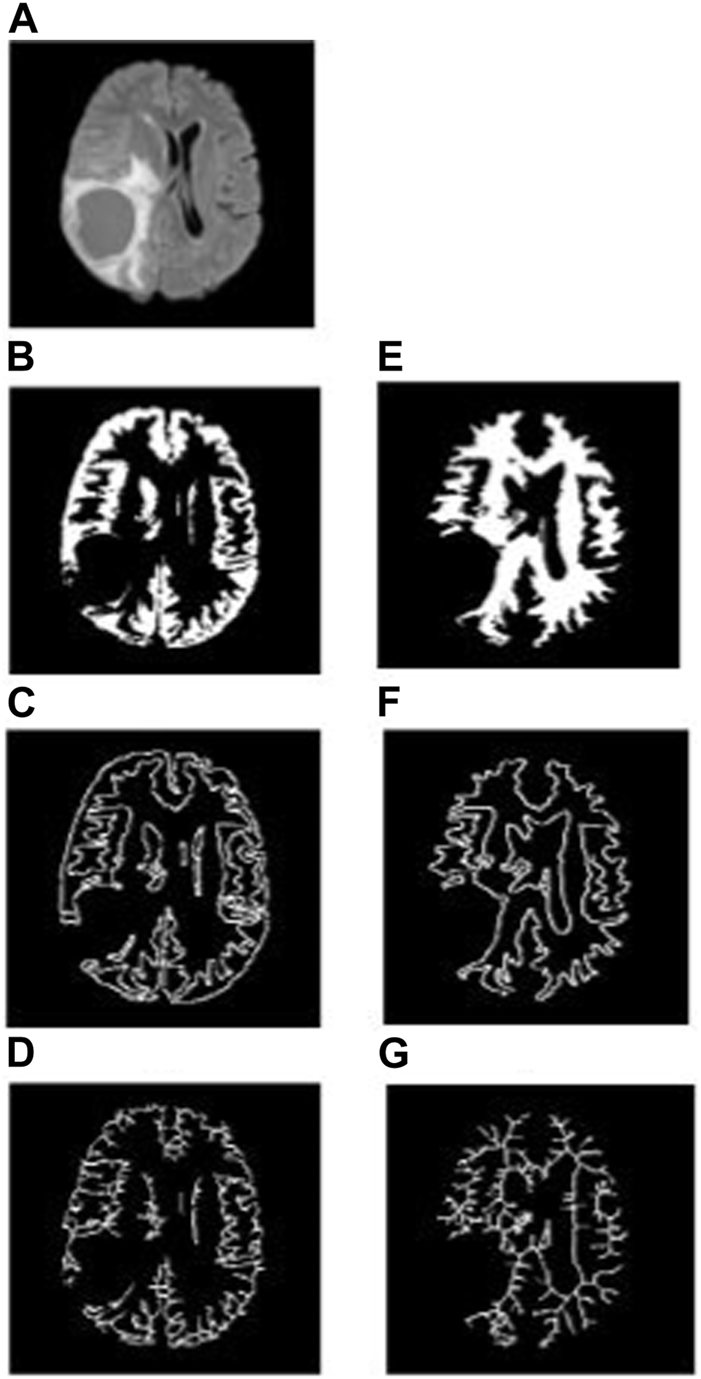

2.4.3 Fractal dimension analysis of non-tumorous regions in LGG and HGG patients

To analyze the non-tumorous regions, first, we segmented the GM and WM from the T1-weighted MRI using SPM12 software. Furthermore, the corresponding tumor region was subtracted from the GM and WM regions to ensure that only the non-tumorous brain regions remain, as shown in Figure 1. Then, on the non-tumorous whole brain, GM, and WM images, FD values for the general structure, boundary structure, and skeleton were obtained using the box-counting method by adopting similar steps as given in the previous section. Figures 4, 5 show the general structure, boundary, and skeleton of a typical LGG and HGG patient. In total, we have six FD features for the aforementioned non-tumorous regions (three for GM and three for WM, where the three features are general structure, boundary, and skeleton).

FIGURE 4

(A) FLAIR image of a typical LGG patient, (B–D) general structure, boundary, and skeleton of the non-tumorous GM region, and (E–G) general structure, boundary, and skeleton of the non-tumorous WM region.

3.3 Fractal dimension analysis of non-tumorous brain regions

A similar kind of FD analysis was performed on the non-tumorous GM and WM structures. Table 4 shows the mean, standard deviation, and p-values for the general structure, boundary, and skeleton FD measures of non-tumorous GM and WM regions in LGG and HGG patients. Among the six different FD measures, the skeleton of GM (LGG = 0.942 ± 0.032 and HGG = 0.998 ± 0.024, p = 0.0001) and WM (LGG = 0.931 ± 0.035 and HGG = 0.955 ± 0.024, p = 0.0140) revealed a significant difference in their structural complexity between LGG and HGG patients.

The WM boundary FD values failed to differentiate between LGG (0.991 ± 0.056 (mean ± standard deviation)) and HGG (1.012 ± 0.033), but the GM boundary (p = 0.0025) FD values revealed a significant difference between them (LGG = 1.025 ± 0.045 and HGG = 1.075 ± 0.051). In addition, the general structure of the WM region (p = 0.0013) FD values revealed a statistically significant difference between LGG (1.699 ± 0.029) and HGG (1.744 ± 0.072), while the general structure of the GM region remained statistically insignificant (LGG = 1.693 ± 0.063 and HGG = 1.662 ± 0.053). Future studies using diffusion tensor imaging and GM cortical thickness analysis may confirm our findings on significant differences in FD values between non-tumorous WM and GM regions. Figures 4, 5 show the general structure, boundary, and skeleton for non-tumorous GM and WM structures in a typical LGG and HGG patient.